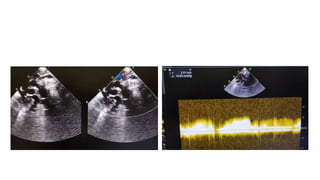

• Repeat Echocardiography showed: Supracardiac TAPVR with vertical

vein obstruction. Moderate size ASD secundum.Dilated right atrium

and ventricle. Severe tricuspid regurgitation 97 mmHg. LVEF 67%.

• Next day echocardiography done.

• It showed: Supracardiac TAPVR with vertical vein stents, Moderate

size ASD secundum, Dilate RA and RV, mild TR 30 mmHg, LVEF 70%

and normal RV function.

Hospital course • RepeatEchocardiography showed: Supracardiac TAPVR with vertical vein obstruction. Moderate size ASD secundum.Dilated right atrium and ventricle. Severe tricuspid regurgitation 97 mmHg. LVEF 67%. • Other laboratory investigation were in normal limits. • Baby admitted in NICU for vertical vein stenting.

Post procedure • Babyshifted to NICU for further management • OG feed started after 2 hours of procedure • Next day echocardiography done. • It showed: Supracardiac TAPVR with vertical vein stents, Moderate size ASD secundum, Dilate RA and RV, mild TR 30 mmHg, LVEF 70% and normal RV function.